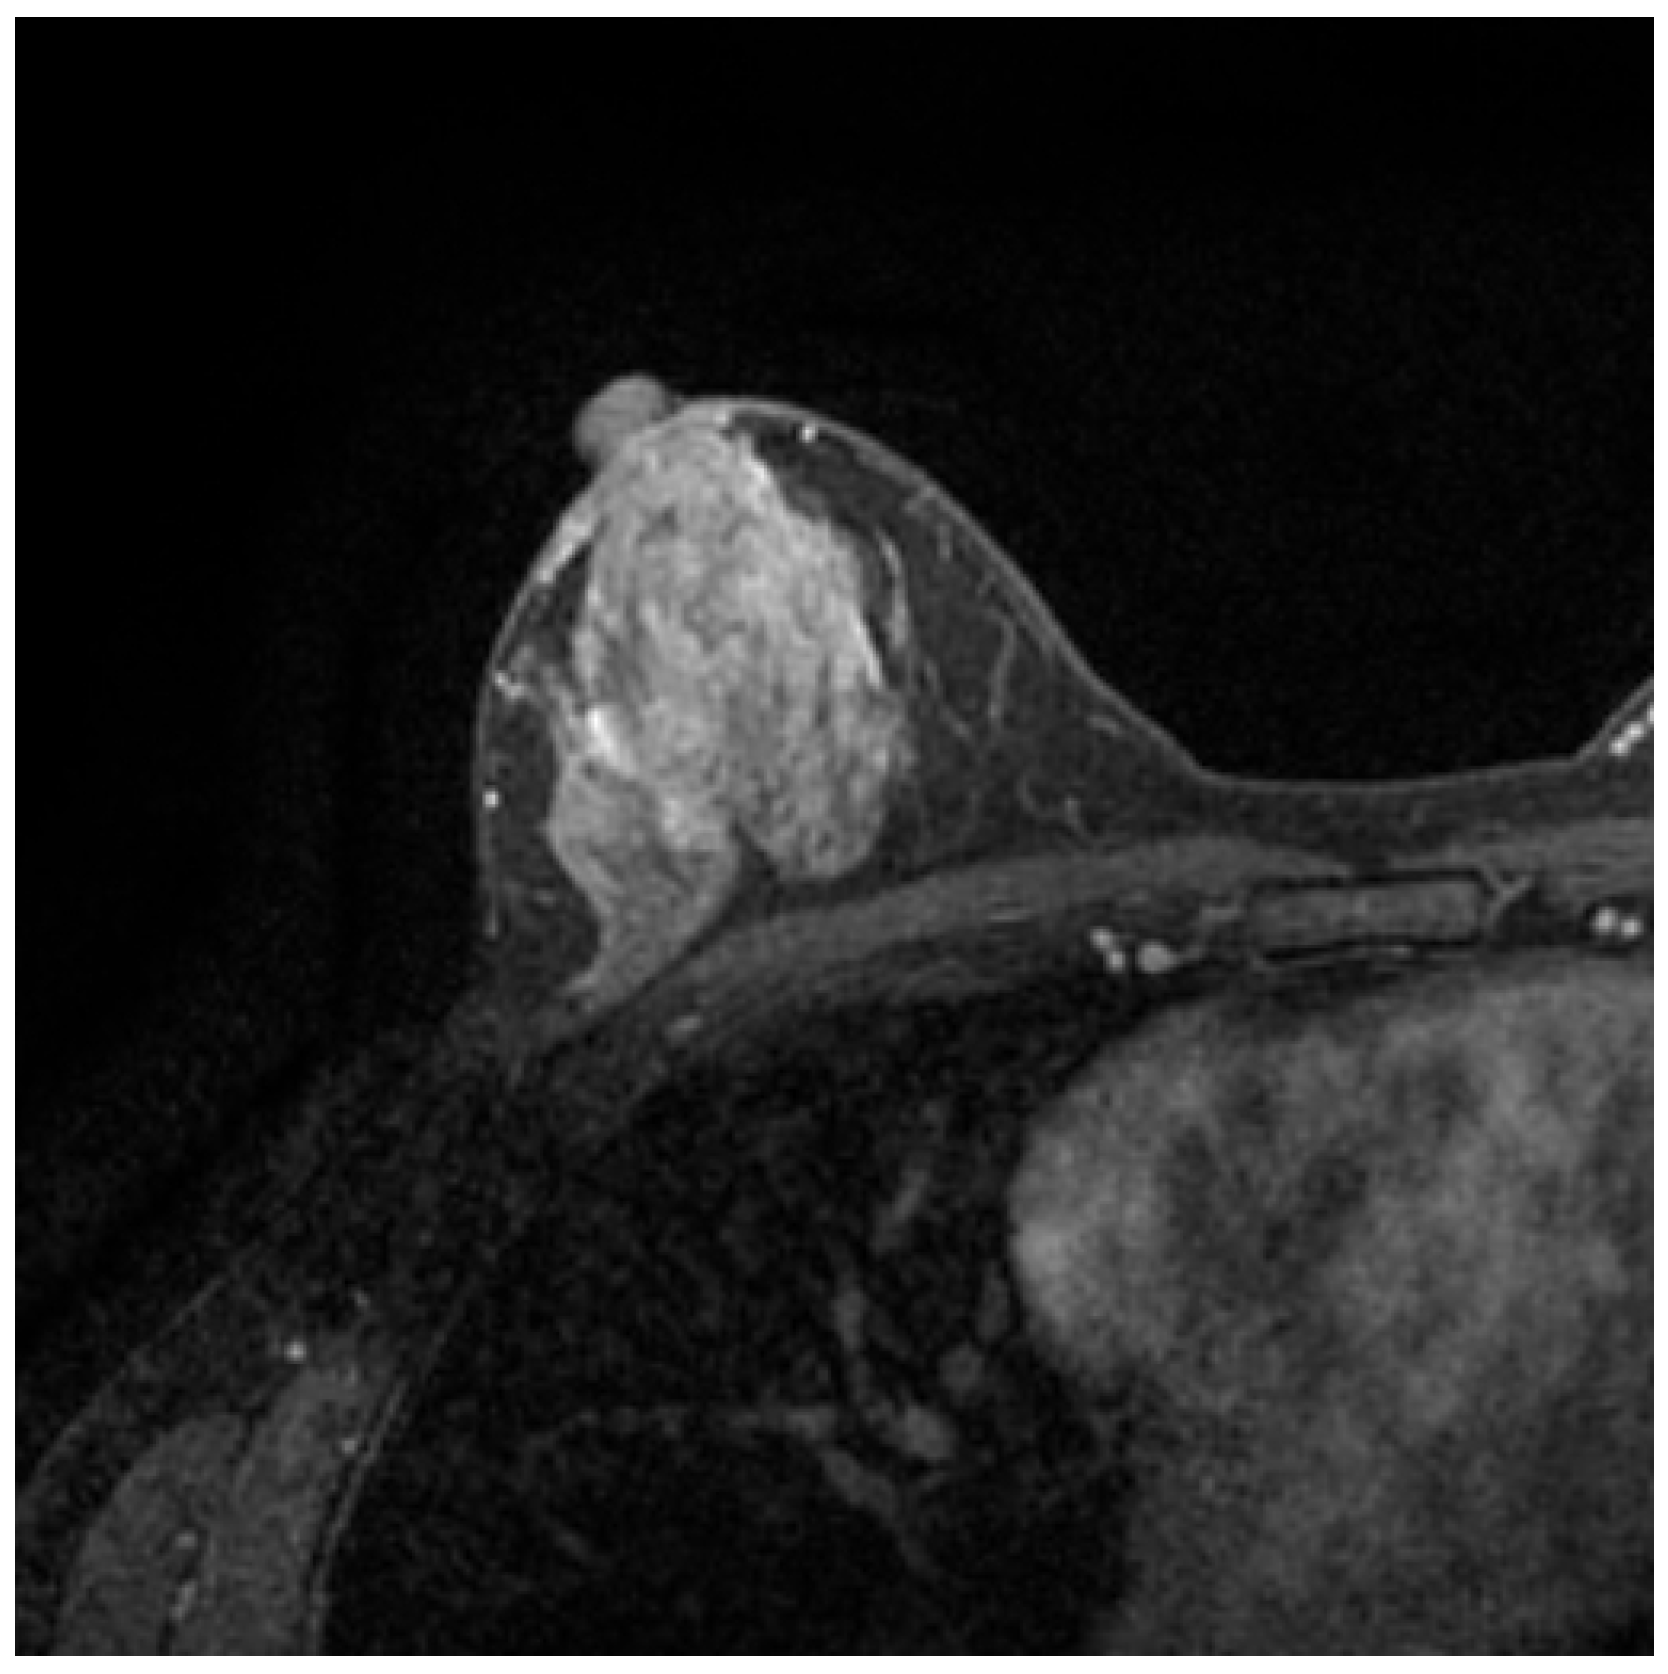

2.1. MRI

- Li, Y.L.; Zhang, X.P.; Li, J.; Cao, K.; Cui, Y.; Li, X.T.; Sun, Y.S. MRI in diagnosis of pathological complete response in breast cancer patients after neoadjuvant chemotherapy. Eur. J. Radiol. 2015, 84, 242–249. [Google Scholar] [CrossRef]

- Waugh, S.; Purdie, C.; Jordan, L.; Vinnicombe, S.; Lerski, R.; Martin, P.; Thompson, A. Magnetic resonance imaging texture analysis classification of primary breast cancer. Eur. Radiol. 2016, 26, 322–330. [Google Scholar] [CrossRef]

- Yao, J.; Chen, J.; Chow, C. Breast tumor analysis in dynamic contrast enhanced MRI using texture features and wavelet transform. IEEE J. Sel. Top. Signal Process. 2009, 3, 94–100. [Google Scholar] [CrossRef]

- Levman, J.; Leung, T.; Causer, P.; Plewes, D.; Martel, A.L. Classification of Dynamic Contrast-Enhanced Magnetic Resonance Breast Lesions by Support Vector Machines. IEEE Trans. Med Imaging 2008, 27, 688–696. [Google Scholar] [CrossRef]

- Torheim, G.; Godtliebsen, F.; Axelson, D.; Kvistad, K.; Haraldseth, A.; Rinck, P. Feature extraction and classification of dynamic contrast-enhanced T2*-weighted breast image data. IEEE Trans. Med Imaging 2001, 20, 1293–1301. [Google Scholar] [CrossRef] [PubMed]

- Rahman, M.; Hussain, M.G.; Hasan, M.R.; Sultana, B.; Akter, S. Detection and Segmentation of Breast Tumor from MRI Images Using Image Processing Techniques. In Proceedings of the 2020 Fourth International Conference on Computing Methodologies and Communication (ICCMC), Erode, India, 11–13 March 2020; pp. 720–724. [Google Scholar] [CrossRef]

- Gubern-Mérida, A.; Kallenberg, M.; Mann, R.M.; Martí, R.; Karssemeijer, N. Breast Segmentation and Density Estimation in Breast MRI: A Fully Automatic Framework. IEEE J. Biomed. Health Inform. 2015, 19, 349–357. [Google Scholar] [CrossRef]